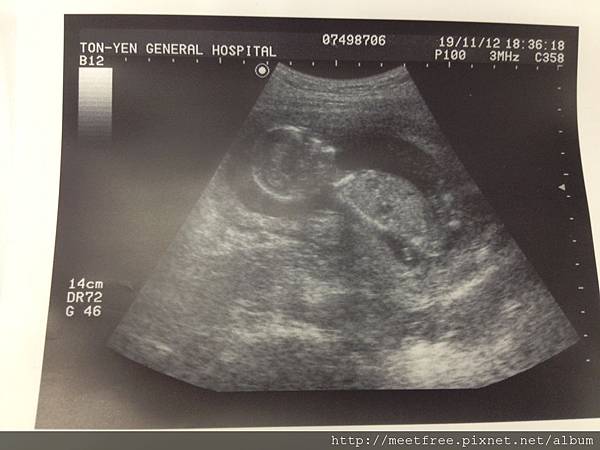

• 【媽咪日記】-第一次"正式"產檢

15W2012/11/19 Mon.(一)

跟以往不同的除了量血壓&體重外,還多一項尿液檢測,

不過就把沾的尿液的試紙放在杯子給護士"瞄"一眼,沒出現怪顏色應該就是過關吧XD

(繼續閱讀...)